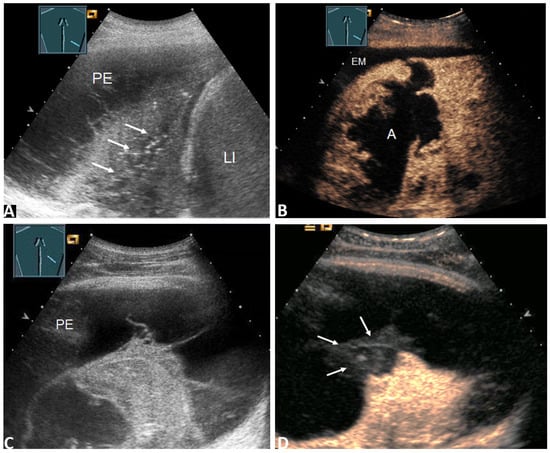

| Enhancement of septa or solid formation (Figure 4D) | 2 (2.4%) | 2 (4.8%) | 0 (0.0%) | 0.494 * |

| No enhancement of septa or solid formation (Figure 5C) | 81 (97.6%) | 40 (95.2%) | 41(100.0%) | |

| Inhomogeneous enhancement of lung consolidation (Figure 5B–D) | 25 (30.1%) | 19 (45.2%) | 6 (14.6%) | 0.004 * |